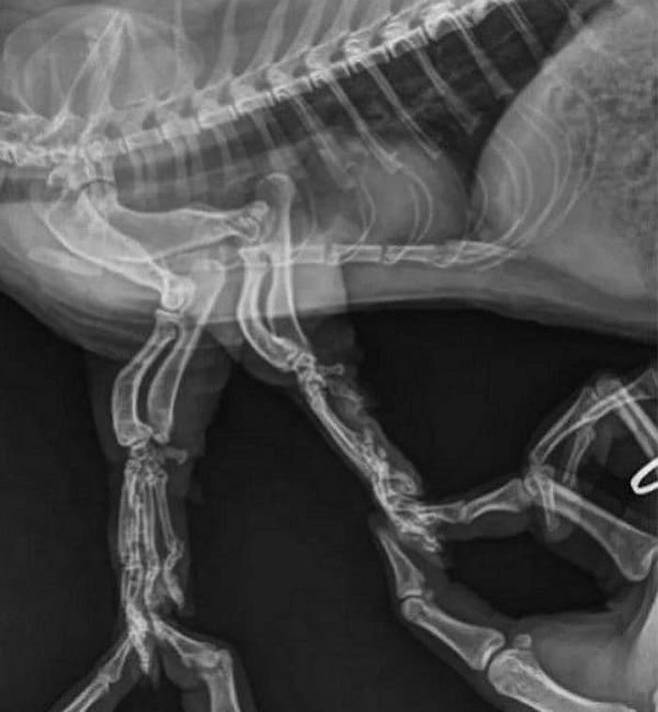

그런데 생각지 못한 일에 부딪히고 말았습니다. 먼치킨 고양이의 다리가 짧아도 너무 짧은 탓에 엑스레이 사진을 찍기 너무 어려웠던 것.

결국 집사는 원활한 엑스레이 사진 촬영을 위해서 먼치킨 고양이의 짧은 다리를 두 손으로 붙잡을 수밖에 없었는데요.

먼치킨 고양이의 짧은 다리를 붙잡고 있지 않으면 도저히 엑스레이 사진을 찍을 수가 없었기 때문입니다.

그렇다면 사진은 잘 촬영이 되었을까. 공개된 사진 속을 보면 먼치킨 고양이의 다리를 붙잡고 있는 집사 손가락까지 찍혀 있음을 확인할 수 있었죠.